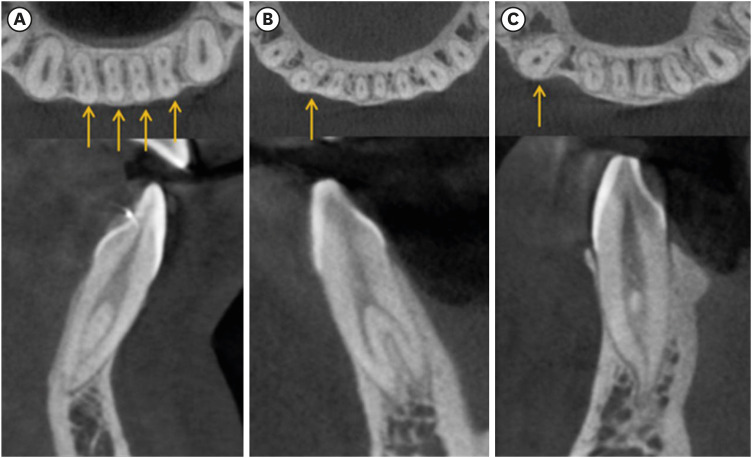

• 3. MnCns (Figure 2B and 2C) [17]:

• Single canal.

• Complicated canal: a) one root and multiple canals or b) 2-rooted.

Figure 2

(A) Mandibular central and lateral incisors with complicated root canals, (B) 2-rooted mandibular canine, (C) 1-rooted/complicated canal mandibular canine.

rde-49-e2-g002.jpg